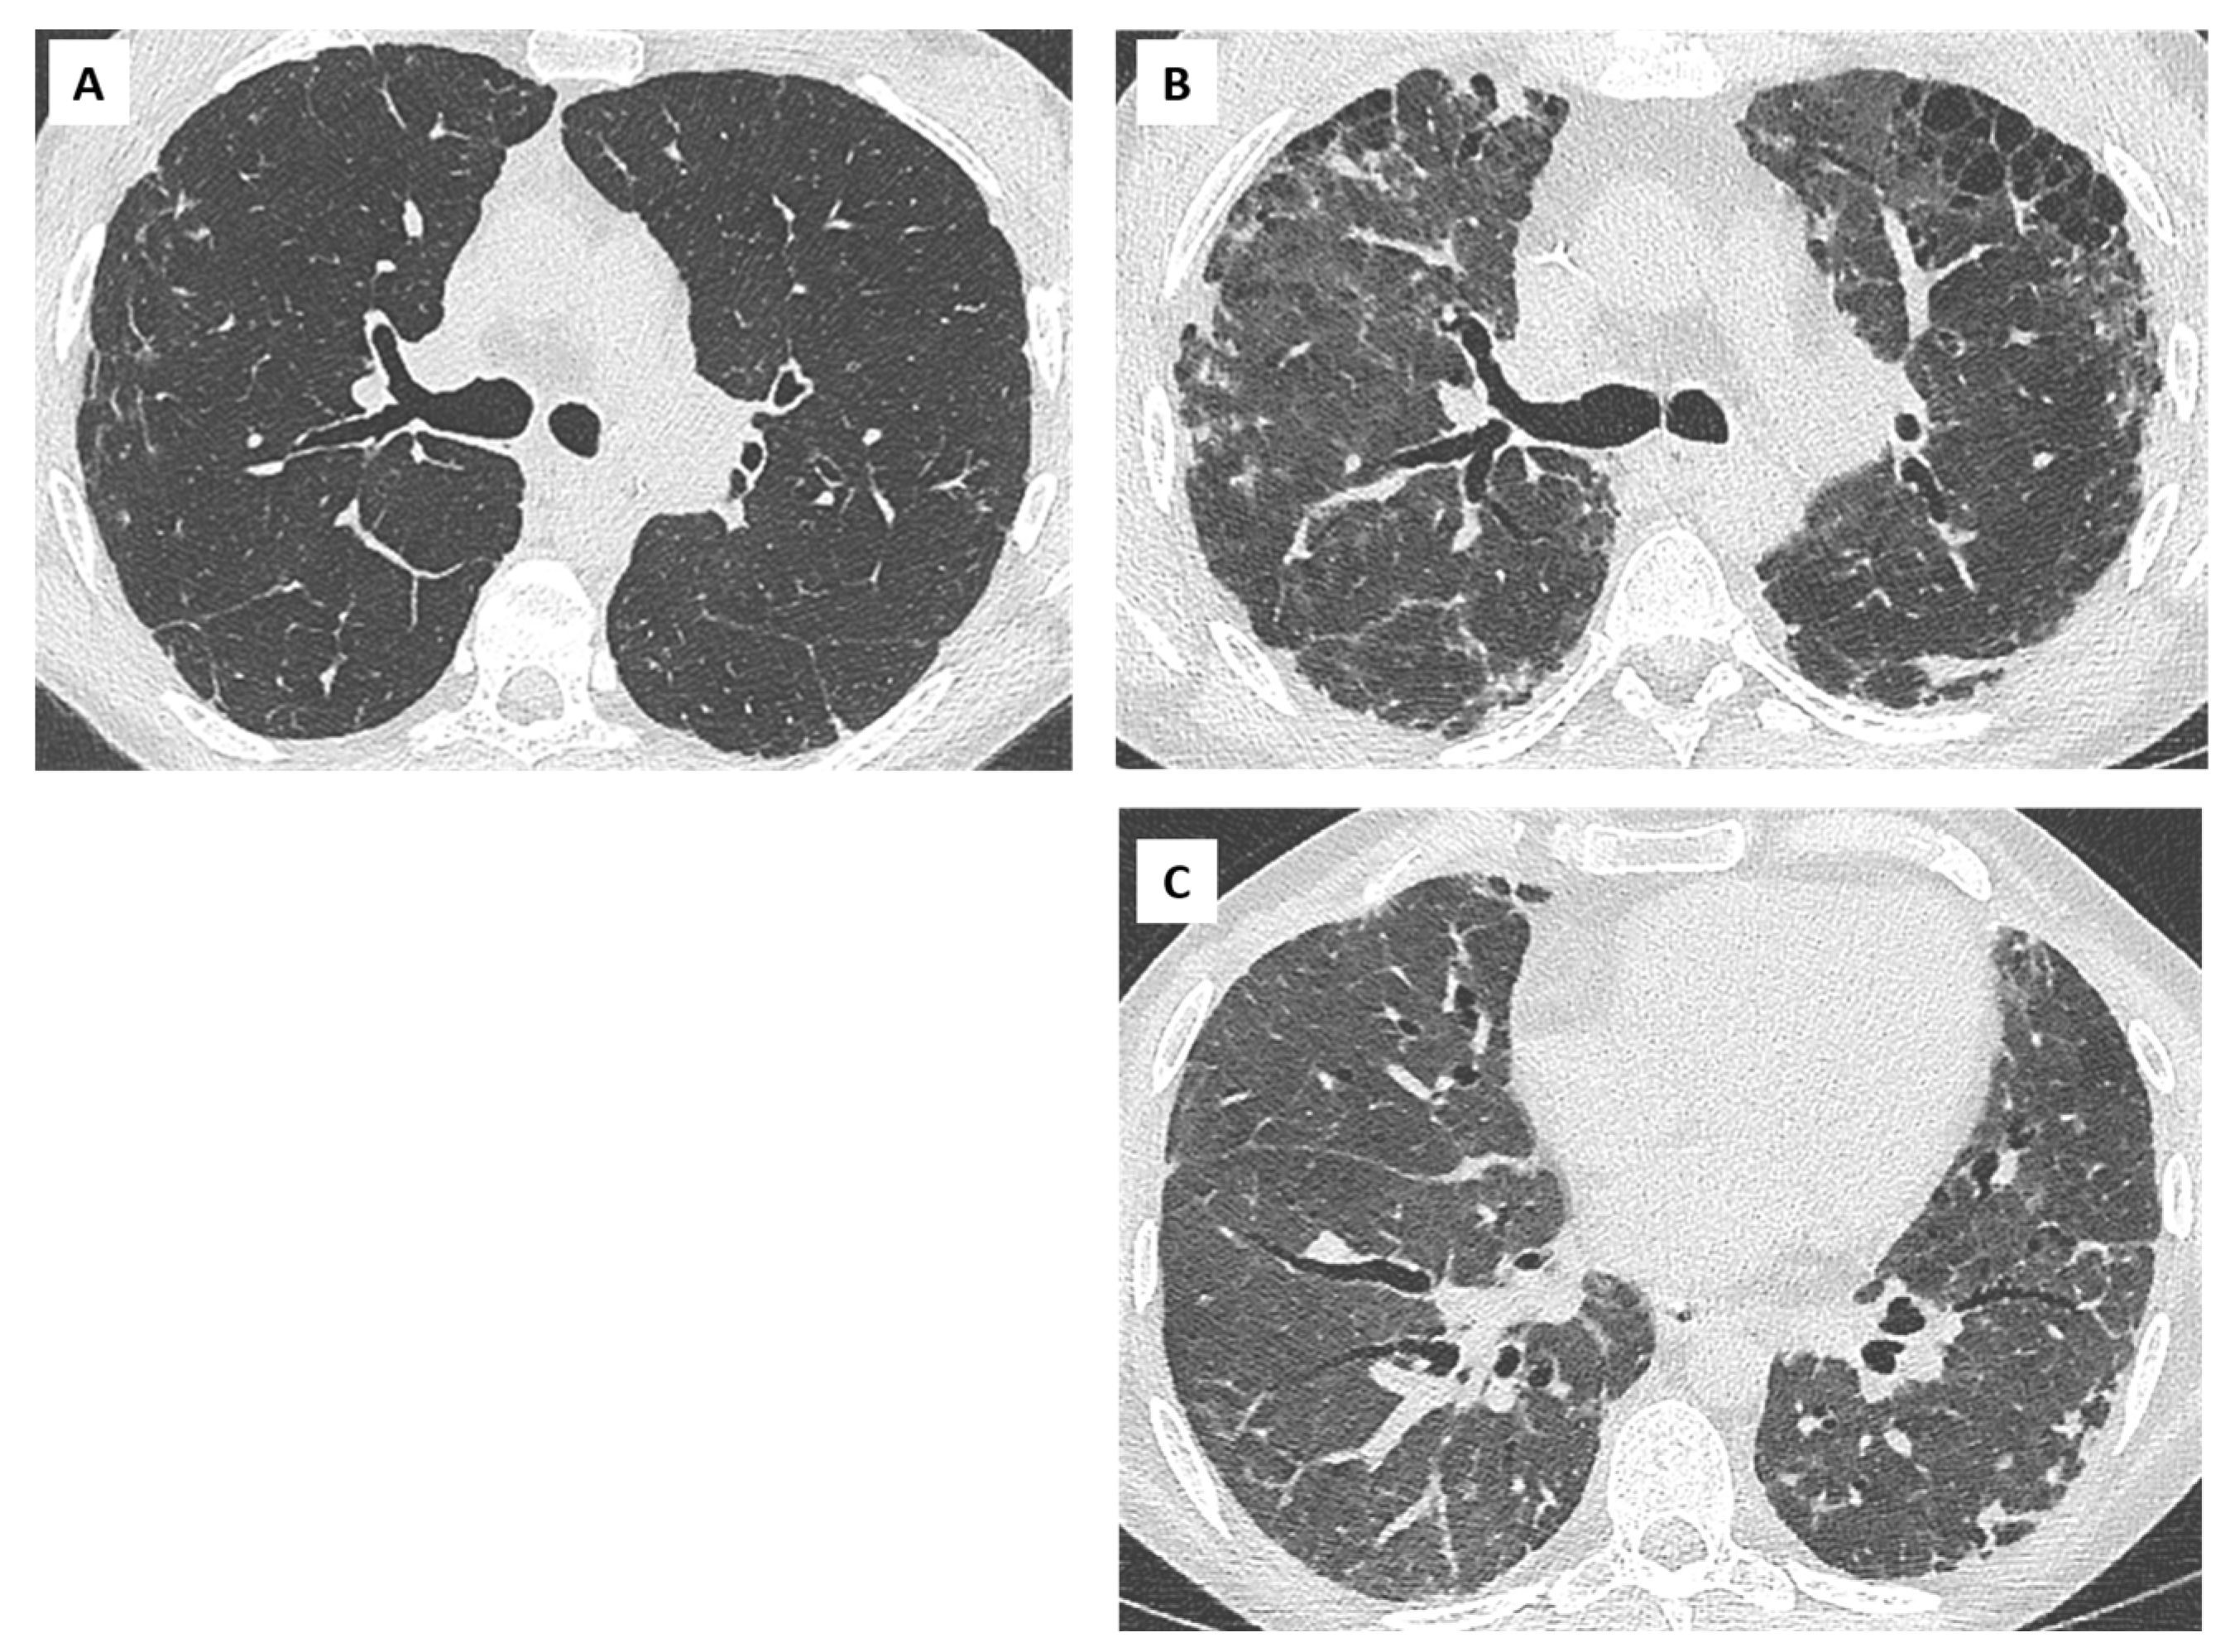

- Ofek, E.; Sato, M.; Saito, T.; Wagnetz, U.; Roberts, H.C.; Chaparro, C.; Waddell, T.K.; Singer, L.G.; Hutcheon, M.A.; Keshavjee, S.; et al. Restrictive allograft syndrome post lung transplantation is characterized by pleuroparenchymal fibroelastosis. Mod. Pathol. 2013, 26, 350–356. [Google Scholar] [CrossRef]

- von der Thüsen, J.H.; Vandermeulen, E.; Vos, R.; Weynand, B.; Verbeken, E.K.; Verleden, S.E. The histomorphological spectrum of restrictive chronic lung allograft dysfunction and implications for prognosis. Mod. Pathol. 2018, 31, 780–790. [Google Scholar] [CrossRef] [PubMed]

- Montero, M.A.; Osadolor, T.; Khiroya, R.; Salcedo, M.T.; Robertus, J.L.; Rice, A.; Nicholson, A.G.; Roman, A.; Monforte, V. Restrictive allograft syndrome and idiopathic pleuroparenchymal fibroelastosis: Do they really have the same histology? Histopathology 2017, 70, 1107–1113. [Google Scholar] [CrossRef] [PubMed]

- Verleden, S.E.; Vasilescu, D.M.; McDonough, J.E.; Ruttens, D.; Vos, R.; Vandermeulen, E.; Bellon, H.; Geenens, R.; Verbeken, E.K.; Verschakelen, J.; et al. Linking clinical phenotypes of chronic lung allograft dysfunction to changes in lung structure. Eur. Respir. J. 2015, 46, 1430–1439. [Google Scholar] [CrossRef]

- Byrne, D.; Nador, R.G.; English, J.C.; Yee, J.; Levy, R.; Bergeron, C.; Swiston, J.R.; Mets, O.M.; Muller, N.L.; Bilawich, A.-M. Chronic Lung Allograft Dysfunction: Review of CT and Pathologic Findings. Radiol. Cardiothorac. Imaging 2021, 3, e200314. [Google Scholar] [CrossRef] [PubMed]

- Verleden, S.E.; de Jong, P.A.; Ruttens, D.; Vandermeulen, E.; Van Raemdonck, D.E.; Verschakelen, J.; Vanaudenaerde, B.M.; Verleden, G.M.; Vos, R. Functional and computed tomographic evolution and survival of restrictive allograft syndrome after lung transplantation. J. Heart Lung Transplant. 2014, 33, 270–277. [Google Scholar] [CrossRef] [PubMed]

- Glanville, A.R.; Verleden, G.M.; Todd, J.L.; Benden, C.; Calabrese, F.; Gottlieb, J.; Hachem, R.R.; Levine, D.; Meloni, F.; Palmer, S.M.; et al. Chronic lung allograft lung dysfunction: Definition and update of restrictive allograft syndrome. A consensus report from the Pulmonary Council of the ISHLT. J. Heart Lung Transplant. 2019, 38, 483–492. [Google Scholar] [CrossRef]

- Konen, E.; Weisbrod, G.L.; Pakhale, S.; Chung, T.; Paul, N.S.; Hutcheon, M.A. Fibrosis of the Upper Lobes: A Newly Identified Late-Onset Complication After Lung Transplantation? Am. J. Roentgenol. 2003, 181, 1539–1543. [Google Scholar] [CrossRef]